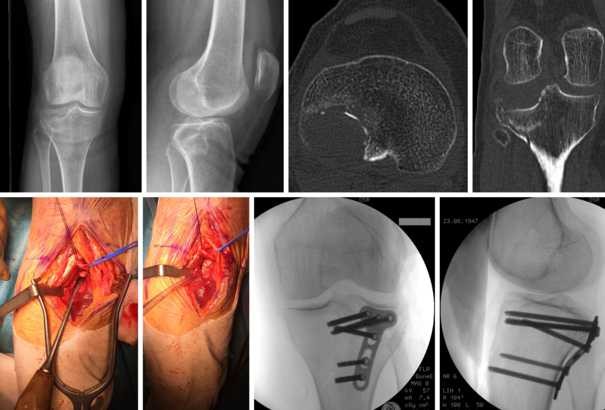

L’innesto dentale osseo detto anche rigenerazione ossea è una tecnica avanzata di chirurgia che permette ripristinare lo spessore di osso perduto tramite il trapianto di osso dallo stesso paziente, o utilizzando dell’osso sintetico biocompatibile o in alternativa osso animale bovino o equino. Innesto osseo a blocco, Questo metodo d’innesto osseo prevede il prelievo di un blocco di osso, oppure di una striscia di osso (12 mm) raccolta dallo stesso paziente (di solito dalla zona del dente di giudizio oppure dal mento) e fissata nell’area problematica da alcune viti di fissaggio. Il rapporto sulle ricerche di settore del mercato Ortopedici per innesto osseo Sostituti 21 fornisce informazioni dettagliate sulla crescita del mercato imminente, le tendenze, le aspettative dei clienti, i miglioramenti tecnologici, le dinamiche competitive, la valutazione dei principali produttori e il capitale circolante nel settore.

Tutto sull’innesto osseo procedura dell’impianto dentale, costo di innesto osseo, innesto osseo per impianti dentali, materiali per innesto osseo dentale, innesto osseo dentale nella mascella e nella mandibola, perdita ossea dentale, innesti ossei dentali, perdita ossea nella mascella e nella mandibola, informazioni su impianti dentali, vitamina per le ossa, innesto osseo eterologo. Il fissaggio dell’innesto è ottenuto mediante l’utilizzo di piccole viti da osteosintesi in titanio o pin di diametro compreso tra i 25 e 2 mm, mentre la perfetta copertura dello stesso avviene attraverso l’eventuale utilizzo di membrane riassorbibili e non e soprattutto grazie ad una chiusura ermetica del lembo mucoso, opportunamente rilasciato dal chirurgo con la tecnica di Rehrmann. L’innesto osseo è una procedura chirurgica che prevede l’inserimento di materiale osseo in zone edentule al fine di recuperare il volume andato perso e di ottenere uno spessore sufficiente per inserire e stabilizzare gli impiantiE’ utilizzato anche a scopi preventivi (“socket preservation”) per riempire il vuoto lasciato dalle radici dei denti subito dopo le estrazioni ed evitare.

IT Innesto osseo sostitutivo PRODENSE® () NOTA Non aggiungere alcuna sostanza supplementare all’innesto L’uso di soluzioni di miscelazione alternative e/o l’aggiunta di altre sostanze alla miscela potrebbero alterare la sicurezza e l’efficacia del presente prodotto Alcune sostanze, come il midollo osseo o il. Il tessuto osseo per l'innesto viene prelevato dal mento o dalla parte posteriore della mascella e posizionato laddove è presente la mancanza Il tessuto osseo viene fissato tramite viti e coperto da una membrana Tra i 6 e gli 8 mesi dopo l'intervento è possibile passare all'innesto degli impianti. L’innesto osseo è un’intervento che consente di aggiungere un po’ d’osso nelle zone in cui è carente Prendiamo una piccola porzione di osso da un’altra parte del tuo corpo (il mento o l’anca) e la posizioniamo nel sito in cui inseriremo l’impianto.